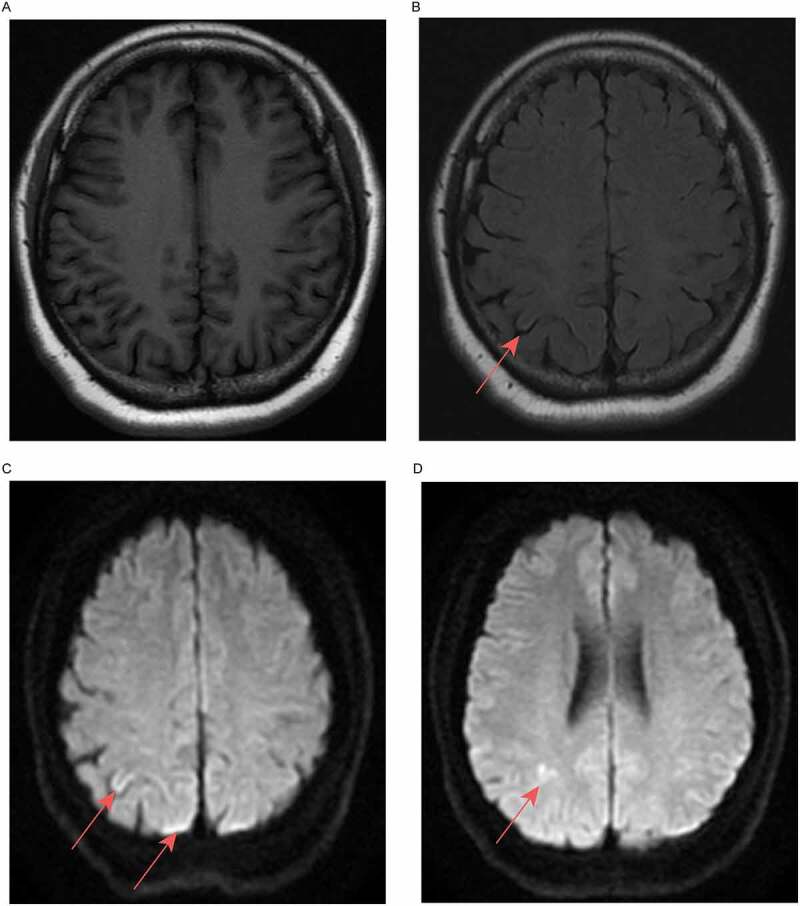

Gerstmann Sträussler Scheinker(GSS)病是一种常染色体显性遗传的神经退行性疾病,以进行性小脑共济失调为特征。到目前为止,具有p.P102L突变的GSS病例主要在高加索人中报道,但在亚洲人群中很少报道。一名54岁的女性患者在医院里步态不稳。去年,她无法稳定行走,偶尔会哽咽,甚至逐渐无法独立行走。在记录了她的病史后,我们发现她在步态问题之前被误诊为精神分裂症。患者的父亲表现出类似的症状,在56岁时被诊断为脑萎缩,但她的女儿目前没有表现出类似症状。到达神经内科后,患者的生命体征和实验室检查均无异常。由于先证者表现为小脑共济失调,并且有明显的家族史,我们确信她患有遗传性小脑共济失调。然后,患者的大脑MRI显示右顶叶皮层有异常信号,额叶有双侧小缺血病变。进行基因分析(包括142个共济失调相关基因),并鉴定出一个杂合突变PRNP Exon2 c.305C>T p.(Pro102Leu)。她的女儿也有同样的杂合突变。该患者被诊断为GSS,最初症状为精神障碍。经过2个月的中医治疗,患者的行走不稳定性下降,情绪波动也比以前小。总之,我们在中国四川报告了一例罕见的GSS病例,以精神障碍为首发症状的家庭最终被确认为GSS PRNP P102L突变。

Gerstmann-Sträussler-Scheinker (GSS) disease is an autosomal dominant neurodegenerative disease, and it is characterized by progressive cerebellar ataxia. Up to now, GSS cases with the p.P102L mutation have mainly been reported in Caucasian, but rarely in Asian populations. A 54-year-old female patient presented with an unstable gait in the hospital. Last year, she was unable to walk steadily and occasionally choked, could not even walk independently gradually. After taking her medical history, we found that she was misdiagnosed with schizophrenia before the gait problems. The patient's father showed similar symptoms and was diagnosed with brain atrophy at the age of 56, but her daughter showed no similar symptoms at present. On arrival at the Neurology Department, the patient's vital signs and laboratory examinations showed no abnormality. As the proband presented with cerebellar ataxia and had an obvious family history, we were sure that she had hereditary cerebellar ataxia. Then, patient's brain MRI showed an abnormal signal in the right parietal cortex and bilateral small ischaemic lesions in the frontal lobe. A gene panel (including 142 ataxia-related genes) was performed, and a heterozygous mutation PRNP Exon2 c.305C>T p. (Pro102Leu) was identified. Her daughter had the same heterozygous mutation. The patient was diagnosed with GSS with mental disorders as initial symptoms. After 2 months of TCM treatment, the patient's walking instability decreased, and her emotional fluctuations were less than before. In conclusion, we have reported a rare case of GSS in Sichuan, China, and the family with mental disorder as the first symptom was finally confirmed with GSS PRNP P102L mutation.